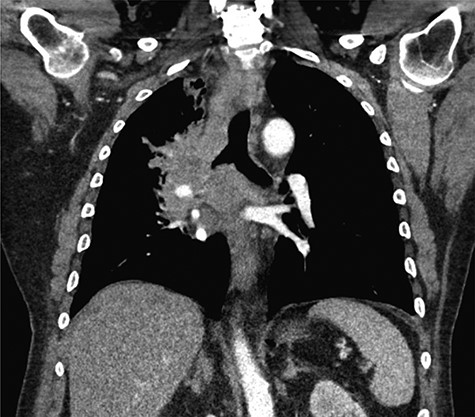

Pathologic analysis revealed that the resected specimens were consistent with poorly differentiated SC carcinoma with immunohistochemical staining reflecting a primary pulmonary source. Tumor cells stained positive for CK5/6 and p40 and were negative for CK7, CK20, villin and TTF1. This established the diagnosis of intra-abdominal metastasis from SC-NSCLC. A radiograph and subsequent CT imaging of the chest confirmed the presence of a right perihilar mass obstructing the right upper and middle lobe bronchi, encasement of the right pulmonary artery branches and extensive bulky mediastinal lymphadenopathy, consistent with primary LC (Fig. 2).

Coronal CT imaging of the thorax demonstrating a large, heterogeneous right perihilar mass with invasion of multiple segmental branches of the right pulmonary artery.